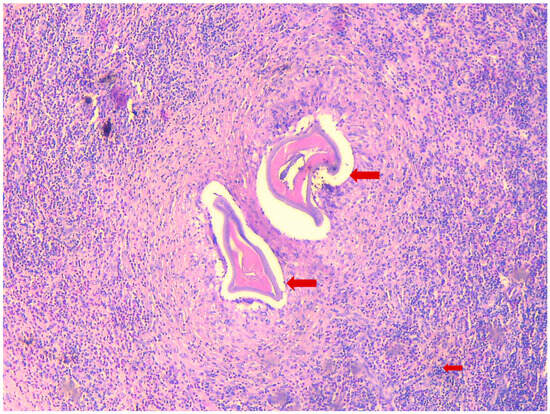

The patient, a 41-year-old female, presented to the infectious diseases outpatient clinic in June 2024 after noticing a swelling in the left groin area that had progressed in size. The first symptoms appeared in April 2024. Initially, the swelling resembled a mosquito bite and did not attract the patient’s attention. But the subcutaneous nodule persisted and began to grow steadily over the course of 8 weeks. During the anamnesis, the patient stated that she often traveled to Kefalonia in Greece. Her last trip before the medical clarification and excision was in August 2023. Symptoms were relatively mild and limited to mild itching at the site of the swelling. The patient reported no systemic symptoms and stated that she was in good physical condition. There were no relevant prior diseases, except a mild iron deficiency syndrome. The complete blood count was unremarkable, but the differential blood count revealed a slight eosinophilia (407 cells/µL and 9.2%, respectively). Three consecutive stool analyses for parasites were negative. Ultrasound examination revealed the swelling to be an encapsulated, easily displaceable mass measuring 3.9 cm in length, 2.6 cm in width, and 1.5 cm in depth. The mass was partially filled with fluid. The MRI confirmed the result of the sonographic examination, with the growing mass being diagnosed as an unclear tumor (Figure 1). It was decided to surgically remove the mass in June 2024 and to send the resected tissue to a pathology laboratory for further examination. On macroscopic examination, the tumor presented as a nodular, beige-colored mass with a lipomatous character. The resected subcutaneous adipose tissue presented with panniculitis and focal abscess formation. There was a clear histiocytic demarcation from the tumor mass, which had a chitin-like character and a cystic configuration (Figure 2). The resected tissue did not stain with Grocott methenamine silver, Alzian blue, or Giemsa. Only Periodic acid-Schiff (PAS) staining showed a delicate colorability of the tumor material. In sum, the histopathological examination results strongly suggested a parasitic infestation. Formalin-fixed paraffin-embedded tumor material was transferred to the parasitology lab at the Medical University of Vienna for further clarification. Based on the sections, the symptoms, and the travel history, the presumptive diagnosis dirofilariasis was made, which was proven by a polymerase chain reaction (PCR) specific for D. repens [15] after DNA extraction from the fixed material. The patient was completely free of symptoms after removal of the mass, with simultaneous regression of eosinophilia, thus no antiparasitic therapy was initiated. Abdominal ultrasonography and exploratory echocardiography performed in September 2024 during a follow-up examination of the patient were unremarkable, so there was no evidence of organ involvement.

Figure 2.

Histopathological section of the biopsy, H&E staining, 20×, a histopathologic section of the biopsy with a granuloma and cross sections of dirofilarial; Small arrow shows the inflammatory infiltrate with lymphocytes and eosinophils; Large arrows show cross sections of the worm.